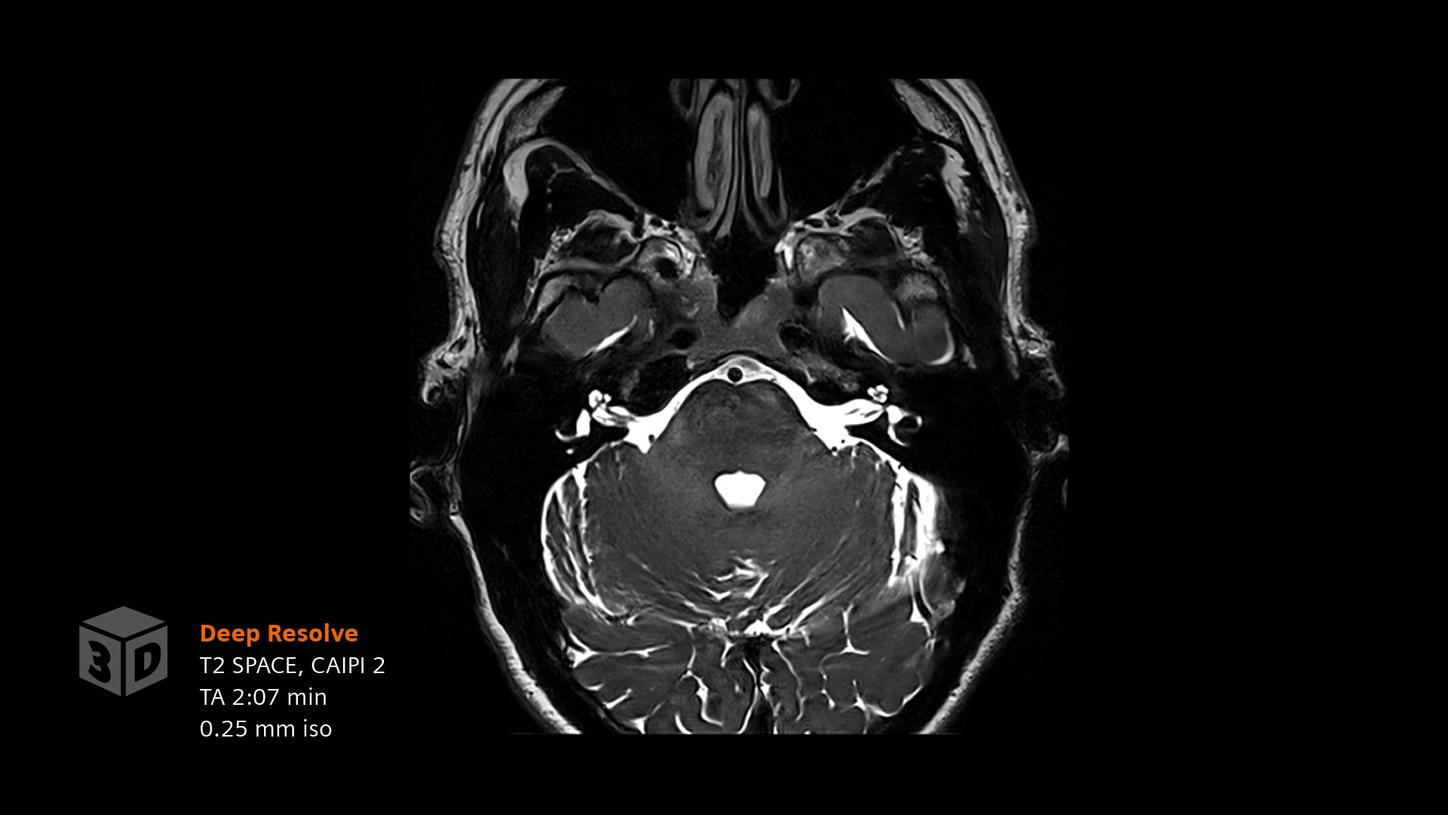

Deep Resolve will be at the forefront of the revolution in MRI acceleration. Deep Resolve will enable our fastest MRI, with images that will have extraordinary clarity, higher clinical productivity, and an even better patient experience. This transformational effect of Deep Resolve is now planned to expand to 3D5, unlocking a new dimension in MRI image resolution and speed.